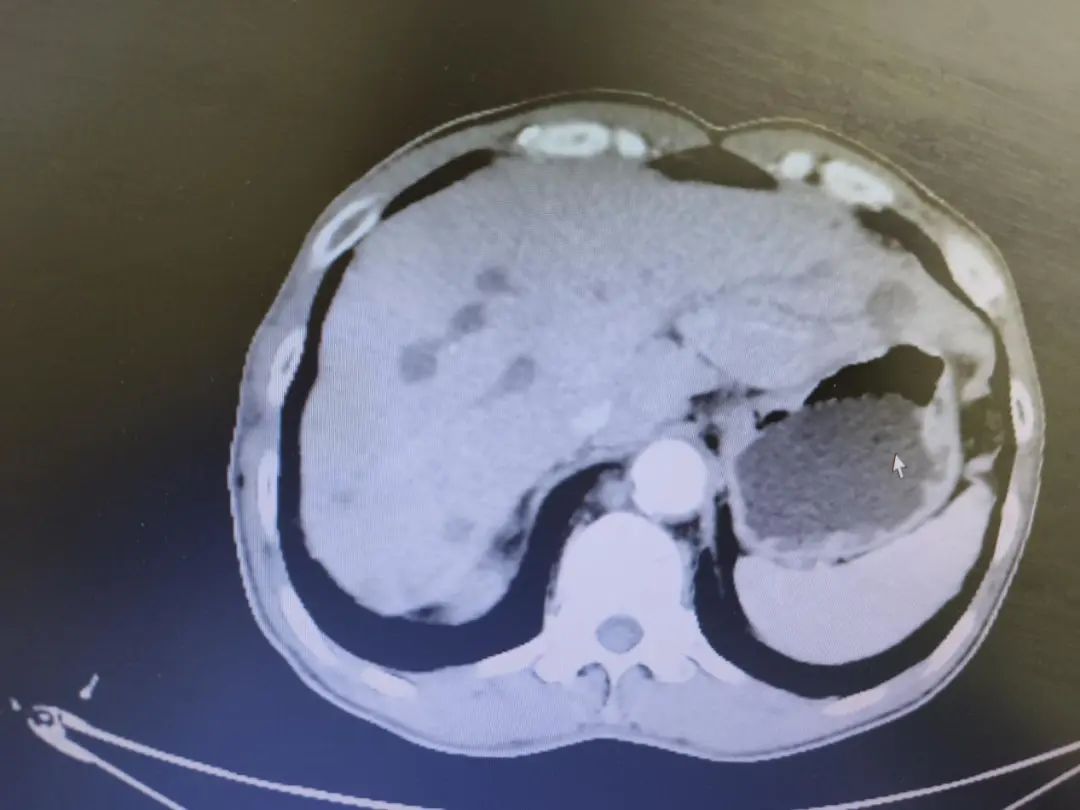

我院2周期化疗后影像(2022年3月28日)